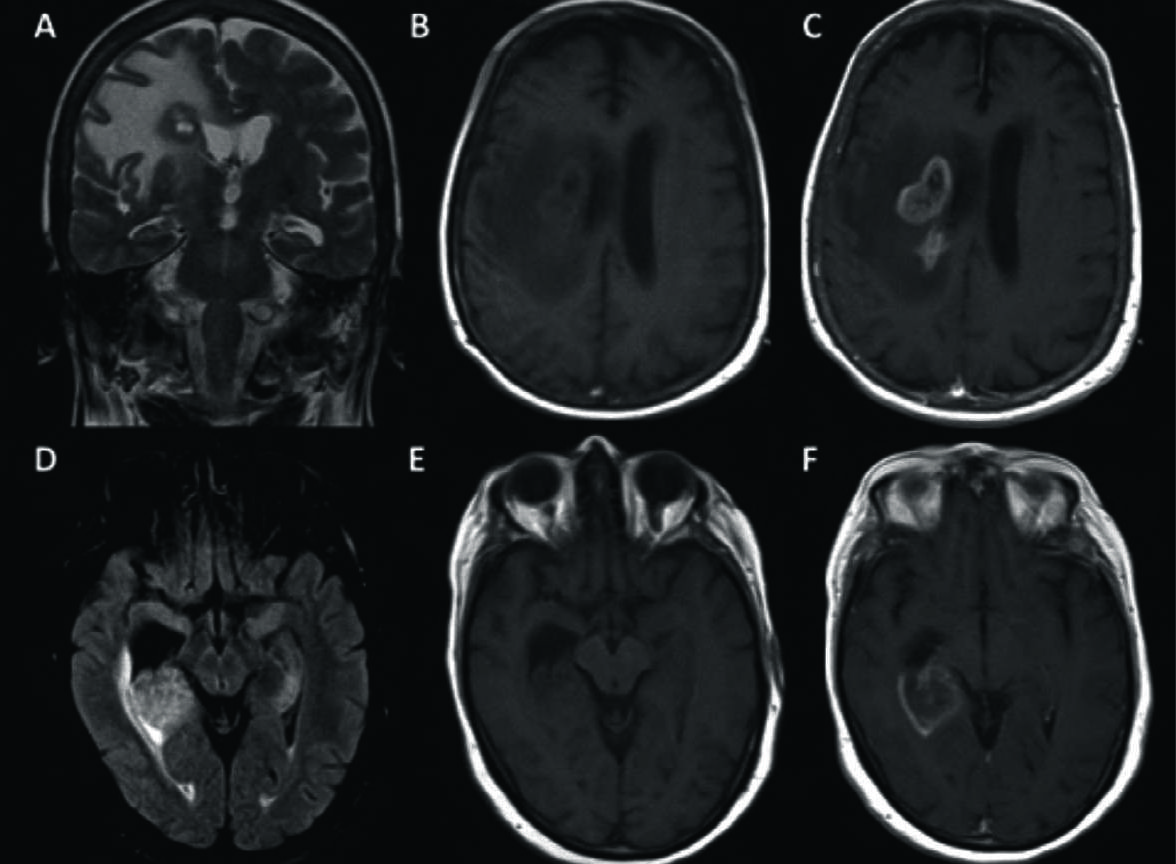

Figura 4

LPSN con necrosis central (2 pacientes).

Se muestran 2 casos de LPSN con focos tumorales que mostraron necrosis.

El primer paciente (A-C) presentó compromiso multifocal con la lesión más importante con centro hiperintenso en T2 (A), hipointenso en T1 (B) y realce en anillo periférico (C) a nivel paraventricular del lado derecho.

El 2º caso (D-F) presentó una lesión única, peri-ventricular profunda, temporal derecha, hiperintensa en FLAIR con atrapamiento del asta temporal del ventrículo lateral y escaso edema (D), isointensa en T1 (E) y realce en anillo con necrosis central (F).

Figura 5

LPSN con lesión única supra-tentorial con hemorragia.

Paciente que se presentó con episodio crítico y cuya RM mostró una lesión peri-ventricular heterogénea, hipointensa en T1 (A), hipointensa en T2 (B) con importante edema en FLAIR (C). En secuencia post-contraste se comprueba el intenso realce con contornos irregulares bien definidos (D).

La secuencia GRE T2* (E) pone en evidencia zonas de artificio de susceptibilidad que corresponden a productos de degradación de la hemoglobina y que traducen hemorragia. En difusión (F) se observa restricción periférica con marcada heterogeneidad.

Solamente 3 (7,5%) casos presentaron focos de hemorragia intra-lesional y focos de necrosis se observaron en 7 casos (17,5%). Figura 4 y 5

En la serie analizada el 85% de las lesiones fueron hipointensas en T1 y el 57,5% en secuencia T2. Sólo en 7 casos se puso en evidencia la presencia de necrosis mientras que 3 lesiones presentaron evidencia de hemorragia. Figura 4 y 5